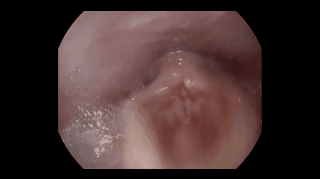

Beatboxer Tom Thum had ENT doctor and laryngeal surgeon Dr Matthew Broadhurst shine an endoscopic camera down his throat while beatboxing: "I wanted to find out how my larynx functioned when beatboxing compared to how it functions normally with speech, and whether or not there were any abnormalities in my laryngeal anatomy. I also had very little idea of what the inside of my throat and all my noise producing mechanisms actually looked like. The results were fascinating yet horrifyingly graphic and will probably make a few people spew in their laps." (via JWZ)